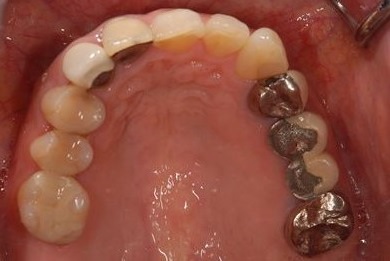

| 性別/年齢 | 女性 / 46歳 | ||||||||||||||||||||||||||||||||

| 治療内容 | メタルボンドセラミックブリッジ3本(メタルボンドセラミック用土台1本)、オールセラミック5本(オールセラミック用土台4本)、オールセラミックラミネートベニア2本 | ||||||||||||||||||||||||||||||||

| 総治療費 | 957,705円 | ||||||||||||||||||||||||||||||||

| 治療期間 | 9ヶ月 |